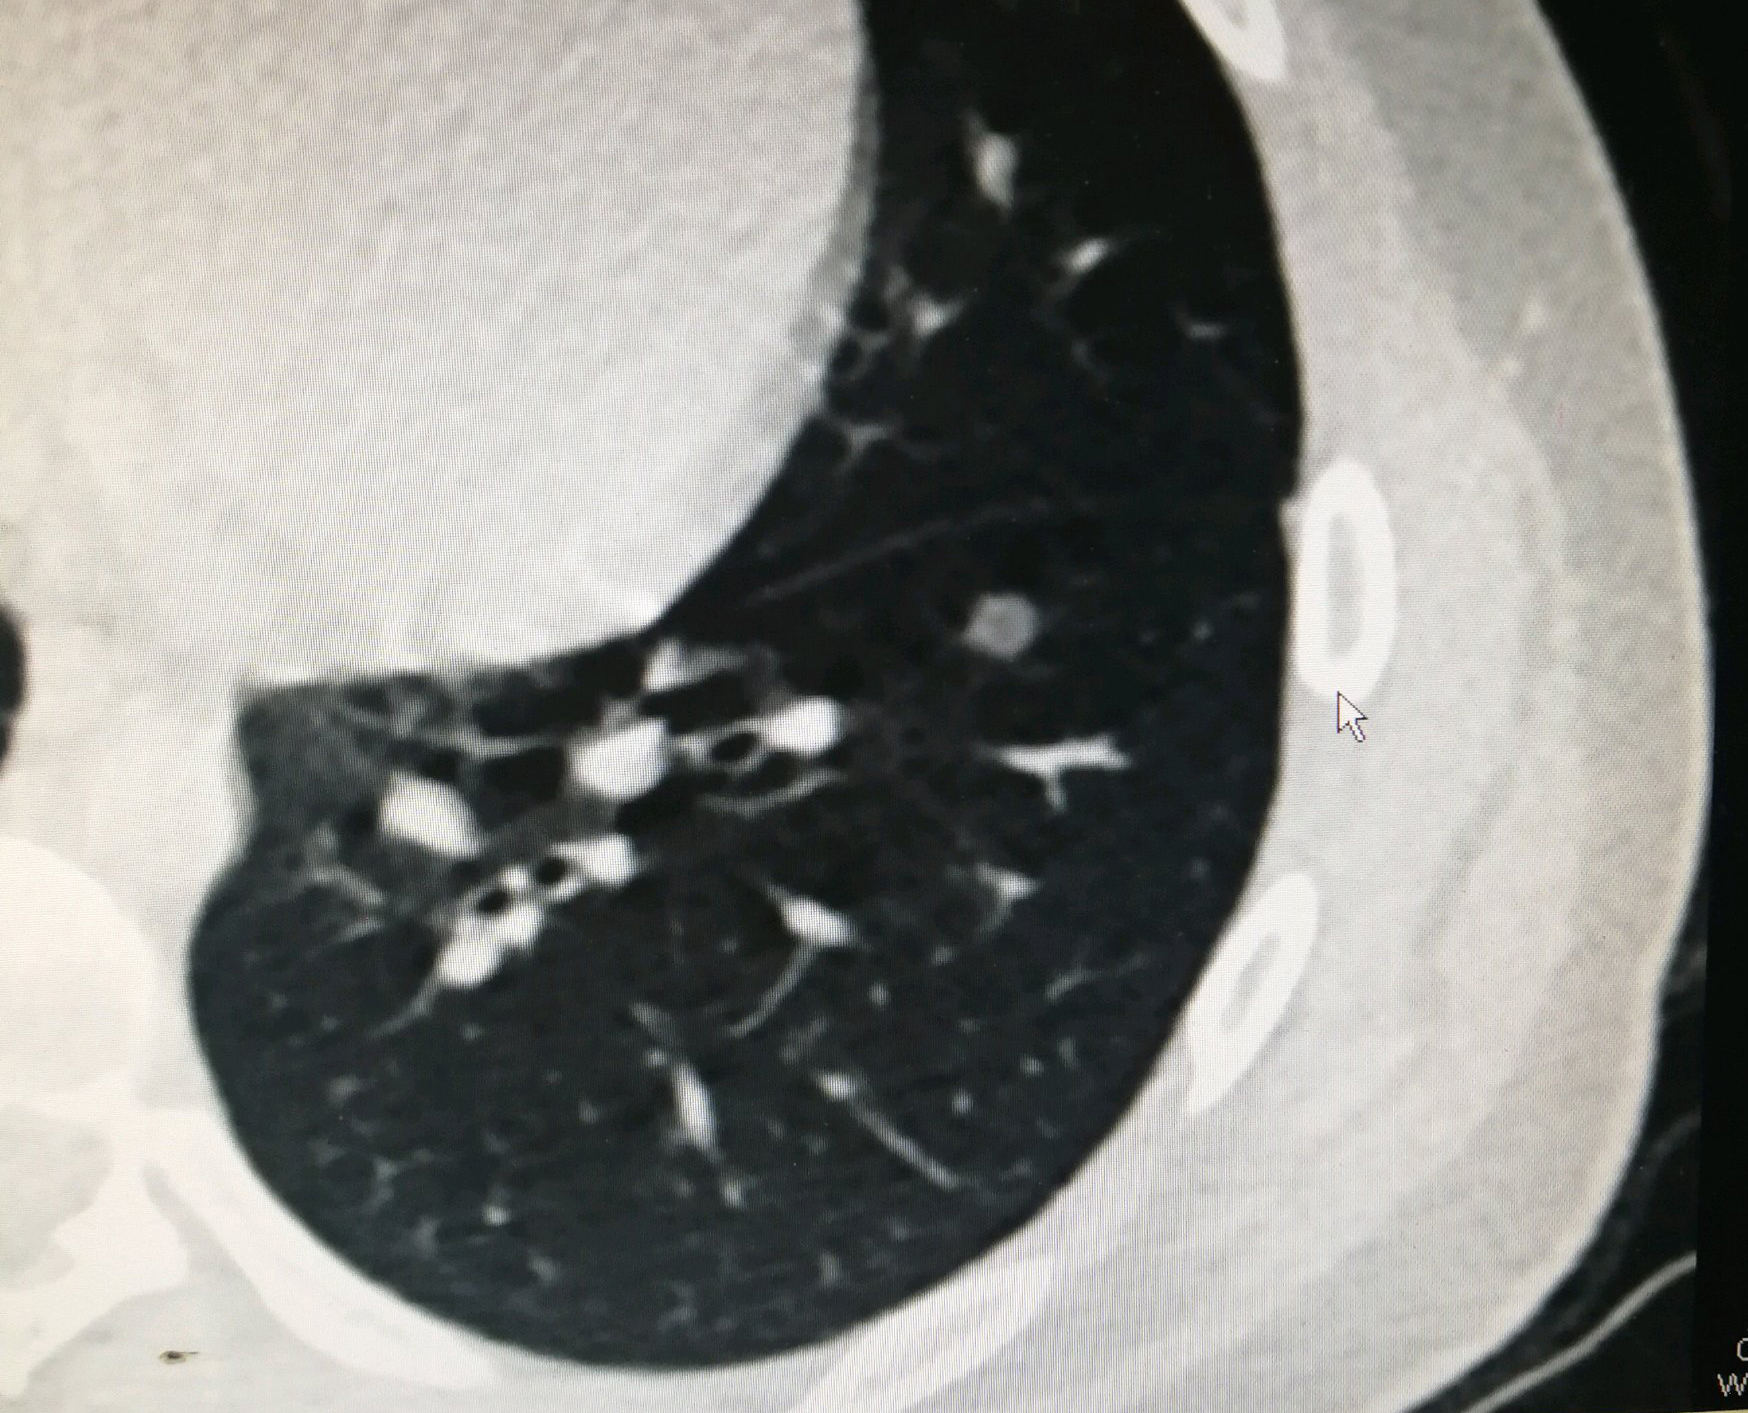

近日,陆军军医大学新桥医院借助术前CT影像仔细研读及人工智能辅助评估系统,在精准的判断下,成功为全国最小年龄磨玻璃肺癌患者,仅有15岁的少年胡彬(化名)实施肺段切除手术,以最小代价切除病灶,顺利救治一名早期肺癌患者。据悉,像这种毫米级别的磨玻璃肺癌,手术切除后估计能接近100%的治愈率。

胡彬是一名初三的学生,一个月前因感冒引起咳嗽发热,在输液治疗都不见好转的情况下,家人将其带到新桥医院检查,为进一步明确诊断,进行了胸部低剂量螺旋CT检查,这一查吓全家人一大跳,检查显示是肺部有磨玻璃。

“这么小的年龄患有磨玻璃?会不会判断有误呢?”在该院胸外科,科室主任戴纪刚教授及其团队对这么小的年龄患有此病表示高度怀疑。对此,专家们将患者的CT检查结果进行了仔细研读,并用人工智能辅助评估系统对其进行仔细分析,系统评估结果显示其恶变概率超过90%。在精准判断的基础上,专家们成功在胸腔镜下为其实施肺段切除术,术后冰冻病理报告为浸润性腺癌。

戴纪刚教授指出,肺癌是我国发病率和死亡率均第一位的恶性肿瘤,目前我国肺癌的5年平均生存率不足17%。提高肺癌的早期诊断和早期治疗率是提高总体肺癌治愈率的关键。近年来低剂量螺旋CT逐渐普及作为筛查早期肺癌的主要手段。在CT筛查过程中发现肺内淡薄的稍高密度结节状的病变,就像是磨玻璃一样,因此称之为“肺磨玻璃结节”。它是肺小结节的一种,但其恶性概率比实性结节更高,对患者的威胁更大。据统计大约34%的肺磨玻璃结节是恶性病变。但好在磨玻璃结节阶段的肺癌往往属于极早期,通过手术治疗可根治,预后较好。提高磨玻璃结节的检出率,精准的识别其中的恶性结节并进行精准手术切除,对于提高肺癌的治愈率至关重要。